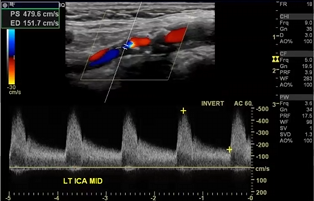

Patient admitted with sudden onset of LT sided weakness and aphasia x 48 hours. Carotid duplex ordered and you obtain this image of RT ICA.

1. Considering patient symptoms, is this a TIA? Why or why not?

2. Considering velocities, what does this image indicate?

3. Describe waveform down stream from this current location.

No because its more than 24 hours

That there is a hemodynamically significant stenosis because the velocities are pretty high at 367.3 cm/s

would be a tardus parvus waveform (slow rise, slow fall)